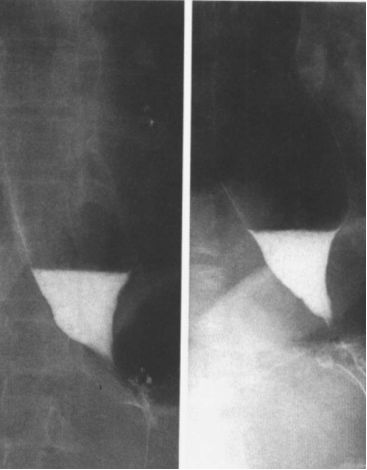

贲门失弛缓:鸟嘴征。

中度贲门失迟缓

重度贲门失迟缓